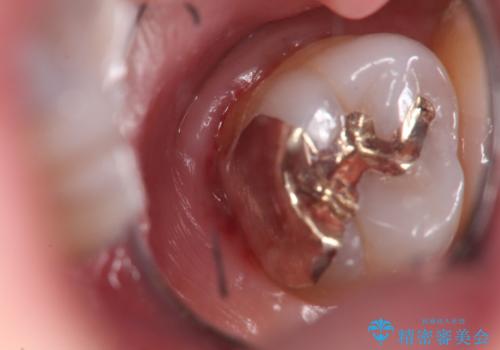

外から見えない位置であるため、セラミックよりも精度を上げることができるゴールド(PGAインレー)で修復していきます。

- 左上7 ゴールドインレー 77,000円費用は治療当時の料金となります

このような虫歯でも丁寧に処置することで問題なく適合の良いインレーを入れることができます。